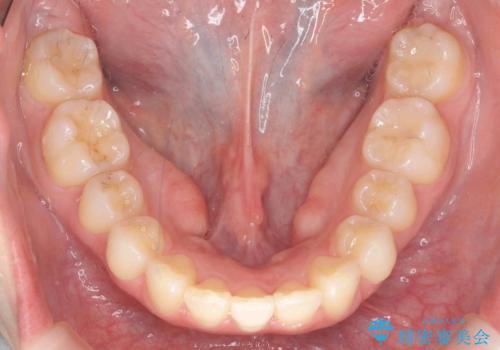

- 上の前歯が出ている感じを治したい、と矯正治療を希望され来院されました。

上顎歯列の突出感を改善すべくIPRを行い、下顎歯列を小さくすることで前歯の角度を大きく是正します、。

下顎歯列は元々前歯が1本少なく小さなアーチでしたが、下顎に合わせ上顎歯列もIPRを行い小さくすることで出っ歯感を大きく改善することが出来ました。